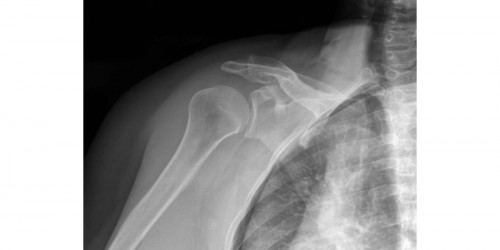

Hi, I am nervous on whether I damaged my surgery. I had RC surgery on May 11th. At 5 weeks post-op the doctor said he believed that I was developing. a Frozen Shoulder. For me to continue PT protocol and he would see me in 2 months. I know longer needed my sling and could do things waist level for height, nothing heavier than 3 lbs. Also I could drive. 3 days later I fell and hit my shoulder. No pain at the time of fall just an ache. I iced it immediately and continued with the ice the rest of the day. Went to PT I told her about the suspicion of a Frozen Shoulder and the fall. The therapist felt around and did not think I damaged anything.l but said I was swollen and inflammed. She continued with the protocol. I always have pain when I leave therapy which last a good 24 hrs. Again somethings I cannot do at all. But this time it was extremely painful. The next day was like the day after surgery l, just pain. My question is do you think I have damaged my surgery or is this pain from PT manipulation on an inflamed shoulder? If I damaged my surgery how will the doctor be able to tell? What happens if I did? Thank you, MaggieMae